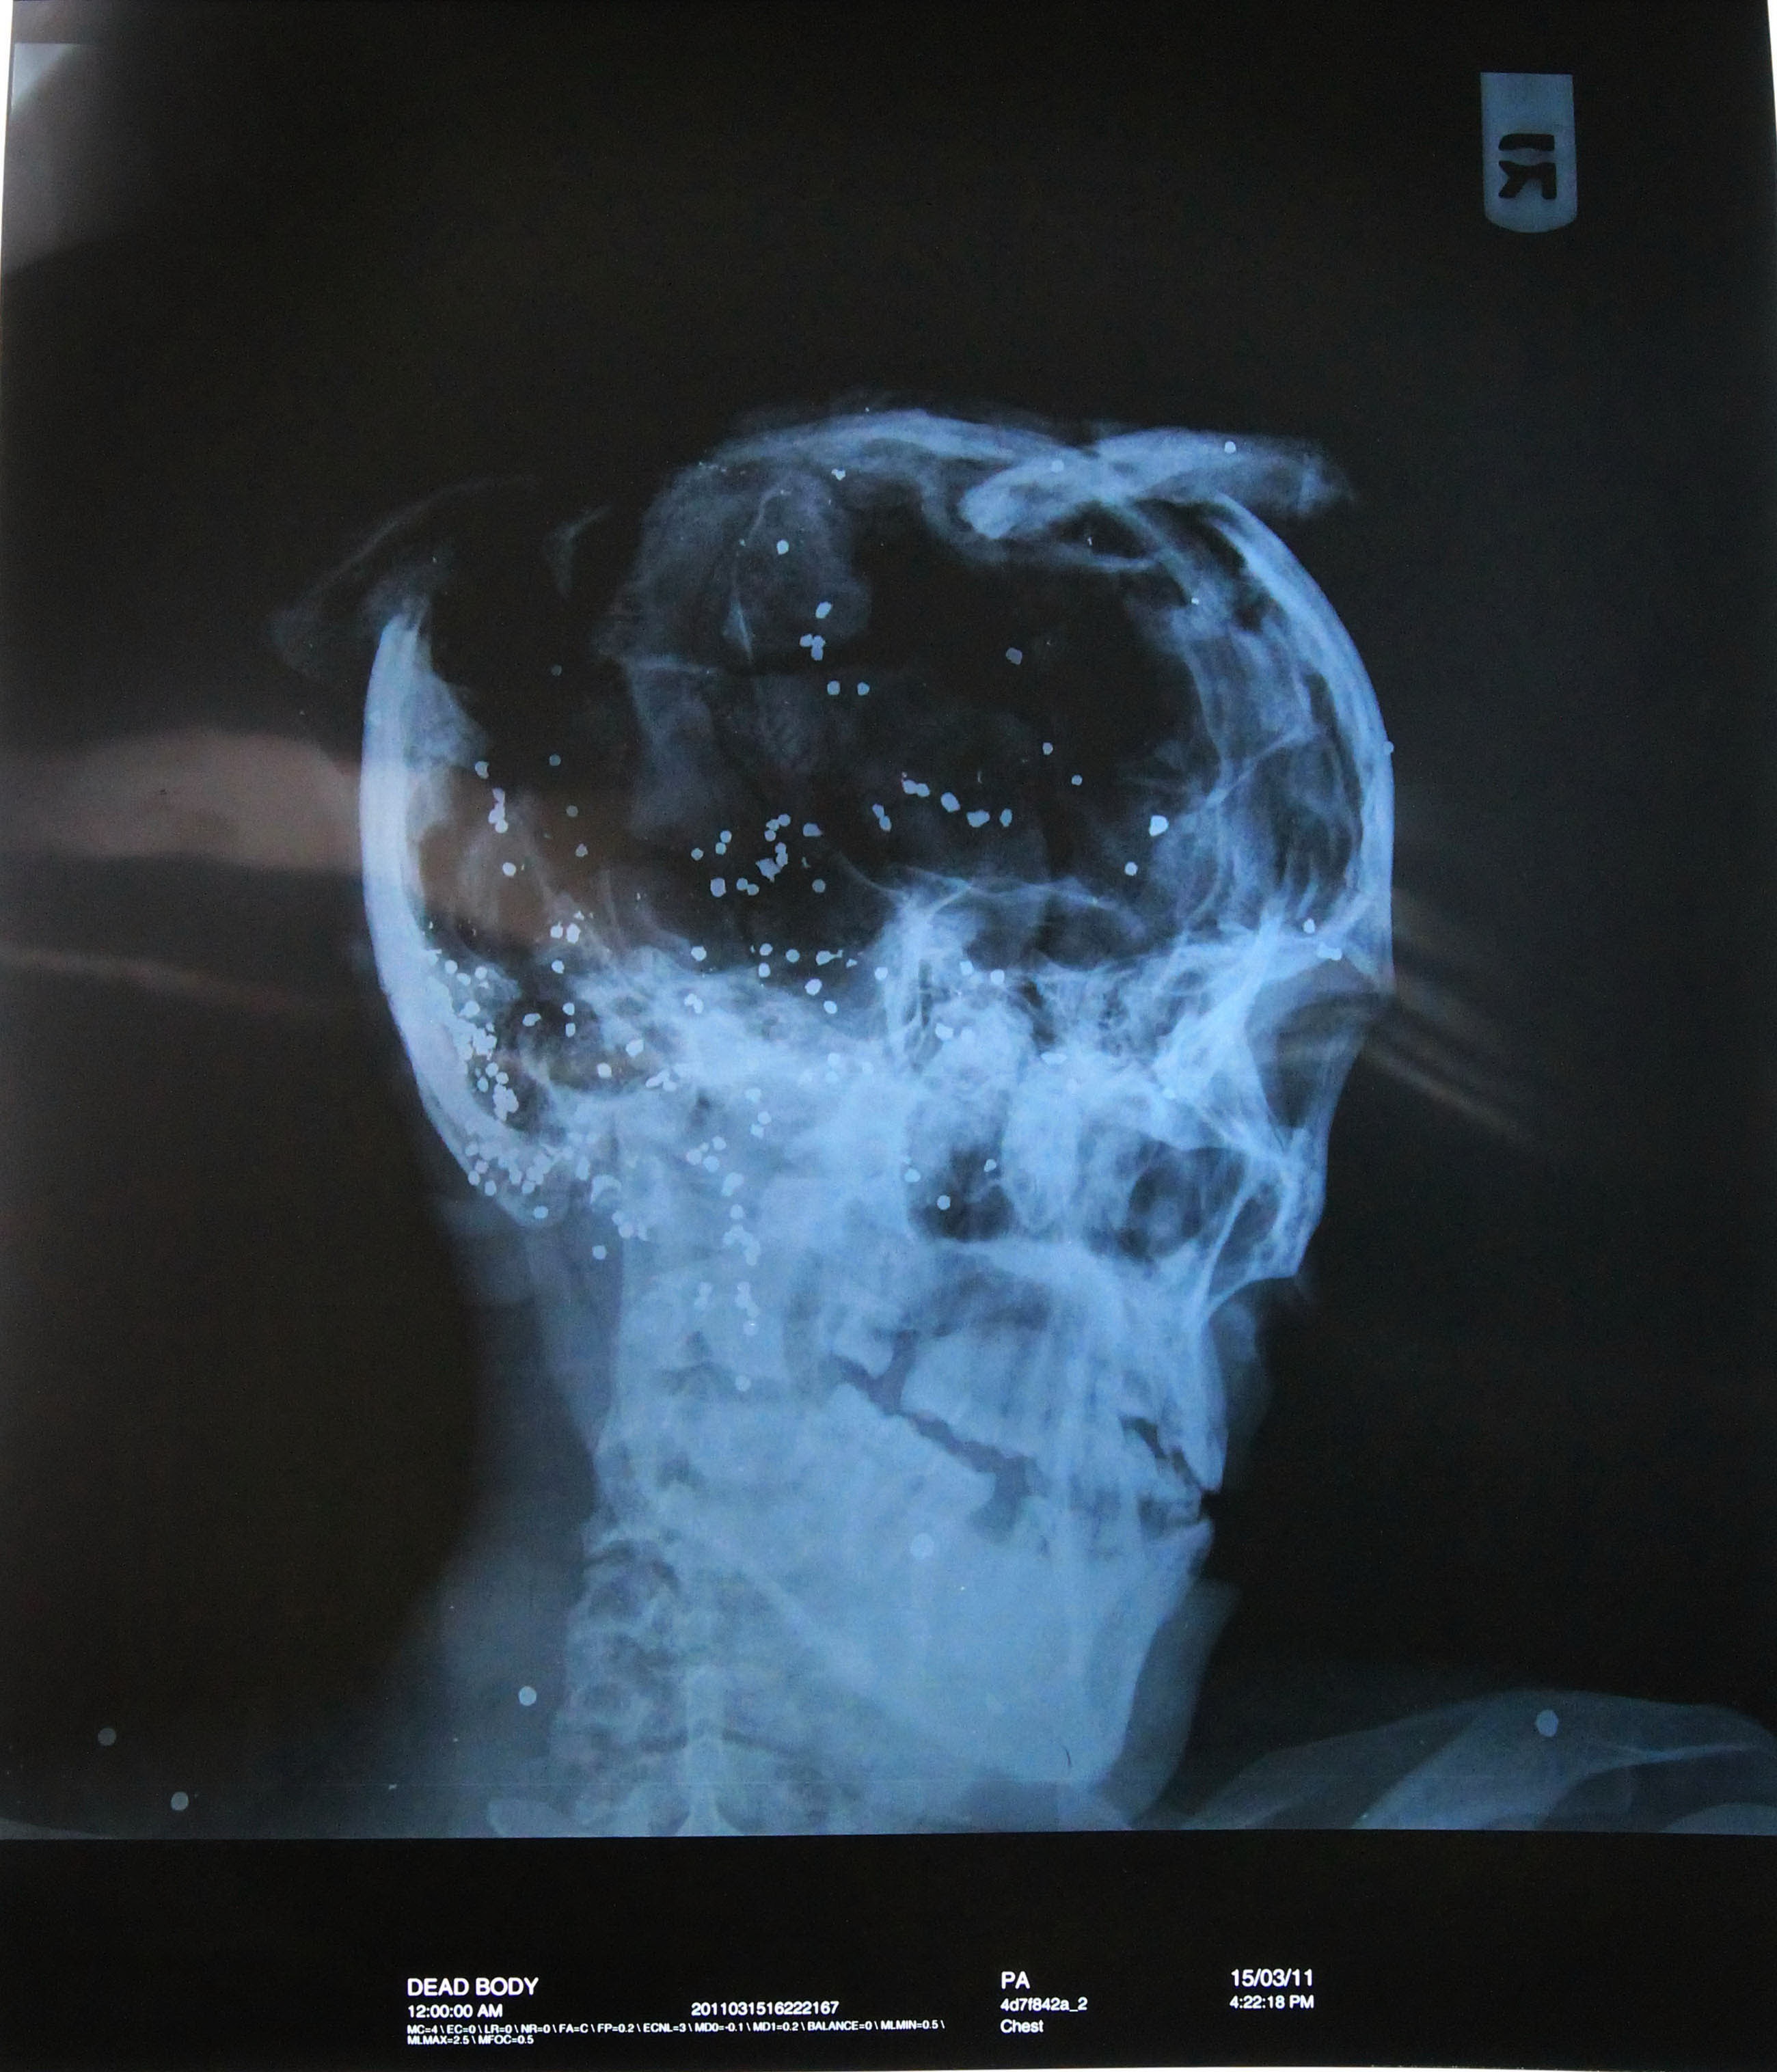

مرآة البحرين (ريبورتاج مصور): ليسوا عبثيين، البحرينيون ليسوا عبثيين، وقدّاس الموت، أو الشهادة، في حياتهم، طقسٌ عابر. مثل كل الناس العاديين، يعشقون الحياة وزخرفها. ويحصل أن يموتوا، والصحيح يُقتّلوا، توقاً إلى حياة لاتشبه الموت أو جنسه. إنه نوعٌ من الحوار الوجودي بين "حياتين". واحدتهما، هي حياتهم الماثلة، حيث الحياة تعادل الموت، ميزاناً، إنما من دون قرينة عضوية: بلا حرية، بلا مساواة، بلا عدل أو شراكة. والأخرى، هي حياتهم المُتخيّلة، والحالمة، في وطن واحد ديمقراطي يحتضن الجميع، الناس فيه مواطنون لا رعايا في مزرعة.

ليسوا بدَعاً بين الشعوب. إنهم ببساطة، يكافحون من أجل شكل آخر للحياة، أقلّ استئثاراً ووحشية. وضدّ شكل آخر من الموت، لا يتحللّون فيه عضوياً، ولكنهم يلمسونه. على هذا، تنشأ ملحمتهم، وتتراكم، منذ 14 فبراير/ شباط. مكلفة طبعاً، قاسية ومؤلمة. لكنهم، ماضون إلى نهايات الملحمة!